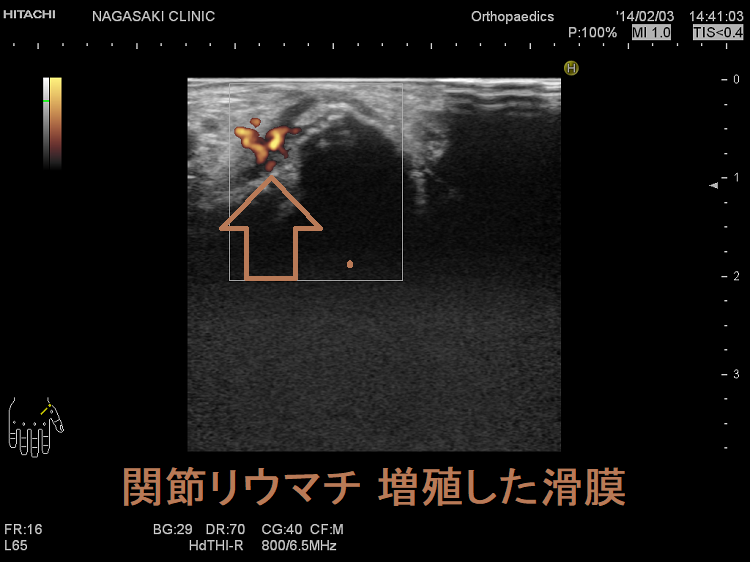

抗CCP抗体陰性なら、増殖した関節滑膜を関節超音波(エコー)検査で見つけます。これには長崎甲状腺クリニック(大阪)と同じレベルの高性能超音波(エコー)診断装置が必要です。

関節エコー検査